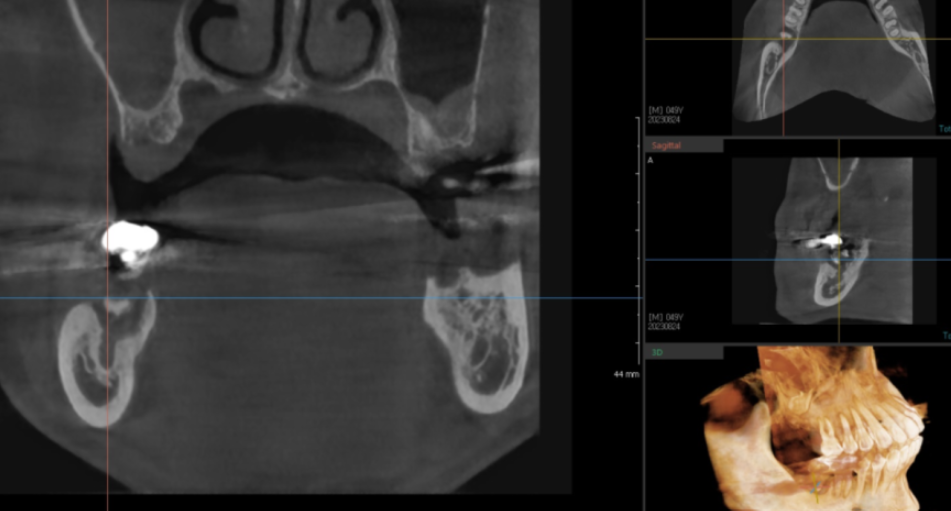

정밀 진단을 위해 ct 촬영을 추가로 했습니다.

치아를 뽑기 전 ct 사진입니다.

치아 주변으로 검정색 웅덩이를 보실 수 있죠?

이게 다 뼈가 녹은 부분입니다.